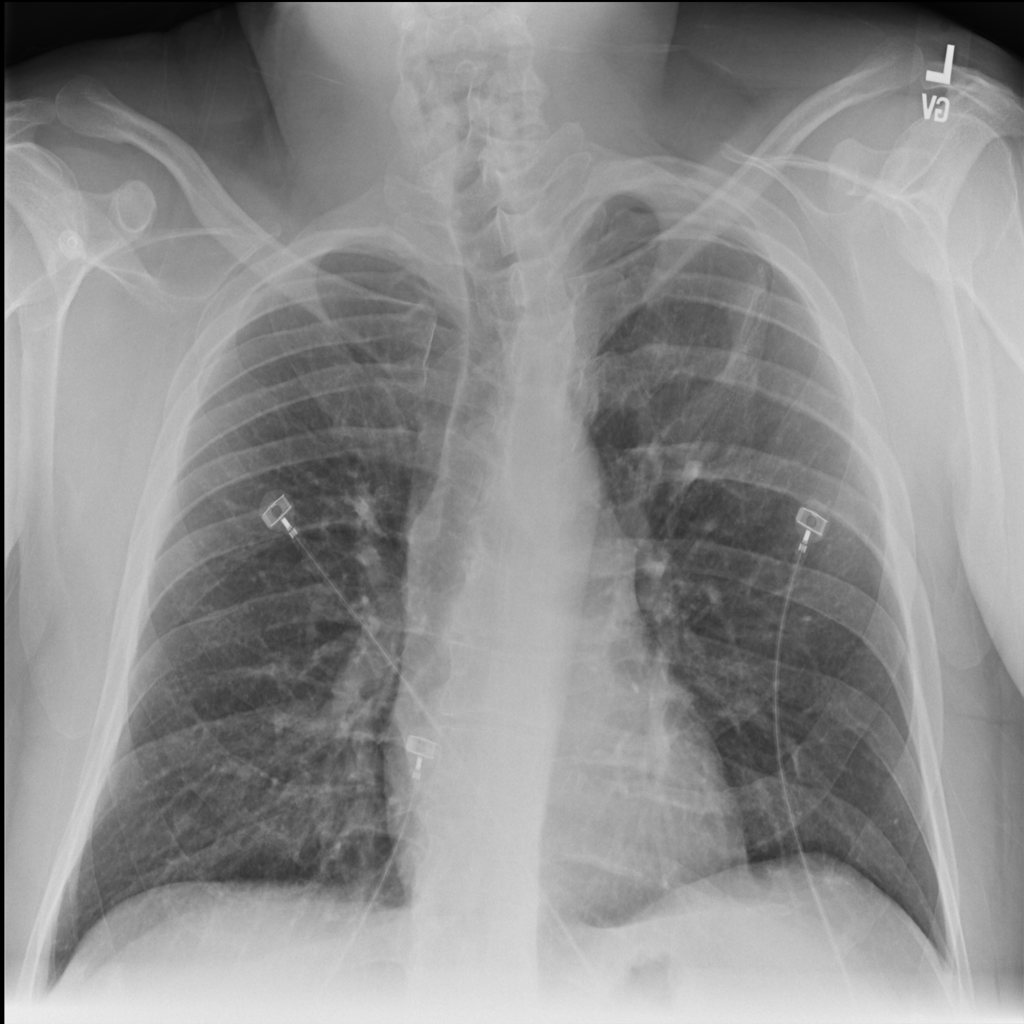

PAT-4639 · IMG-011Pneumothorax

PAT-4639 · IMG-011

AP